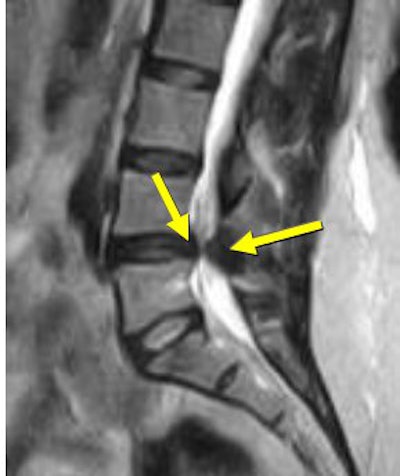

| Above, midsagittal T2-weighted MRI showed increase in stenosis at the L4 level by 2.0 mm with ventral thecal sac compression with axial loading (below). All images courtesy of Dr. Gerald Anzalone. |

Moreover, a number of studies have suggested that conventional MRI and CT are at considerable risk for failing to detect essential narrowing of the spinal canal when only the recumbent patient scanning position is utilized. This has been shown in patients with lumbar spinal pain combined with sciatica, radiculopathy, neurogenic claudication, or suspected lumbar spinal stenosis, according to research conducted by Dr. Jan Willen, Ph.D.; Dr. Barbro Danielson, Ph.D.; and colleagues at Sahlgrenska University Hospitals in Goteborg and Molndal, Sweden (Spine, December 1, 2001, Vol. 26:23, pp. 2607-2614; Acta Radiologica, November 1998, Vol. 39, 6, pp. 604-611; Spine, December 15, 1997, Vol. 22:24, pp. 2968-2976).

Willen and Danielson have also shown that axial-loaded imaging, during recumbent MRI or CT, simulates weight-bearing forces in the lumbar spine, provoking narrowing of the central spinal canal and neural foramina, and increasing the diagnostic accuracy of dynamic spinal stenosis. Dynamic stenosis has been defined in literature as a change in the cross-sectional dural sac area of greater than 15 mm² resulting in a decrease in the dural sac area to less than 75 mm (Spine, December 1, 2001, Vol. 26:23, pp. 2607-2614; Acta Radiologica, November 1998, Vol. 39, 6, pp. 604-611; Spine, December 1, 2001, Vol. 26:23, pp. 2601-2606).